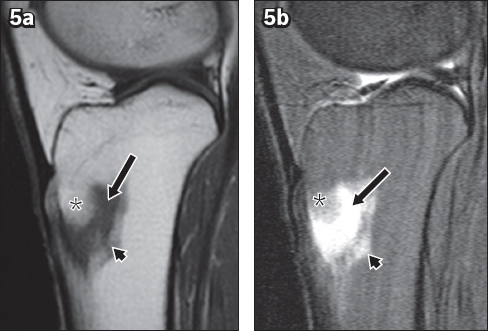

Fig. 5

Intraosseous lipoma of the tibia. (a) Sagittal T1-W and (b) T2-W fat-saturated MR images show that the proximal component of the lesion (*) is isointense to subcutaneous fat. The inferior component is hypointense on the T1-W image and hyperintense on the T2-W fat-saturated image, which is consistent with cystic degeneration (arrows). Mild perilesional oedema is also demonstrated (arrowheads).